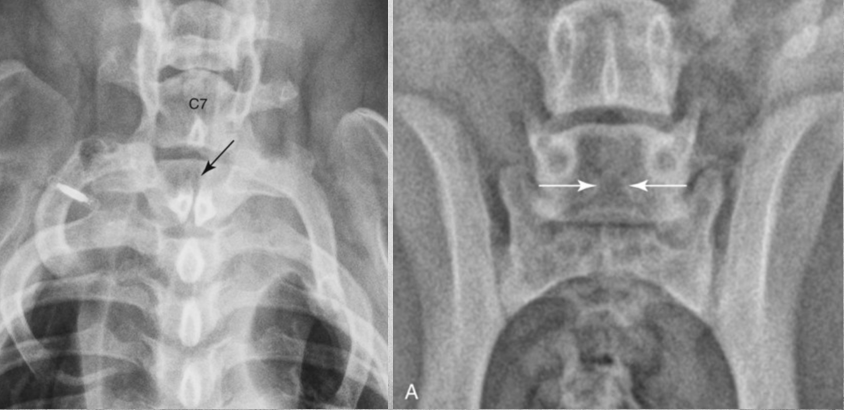

identify issue

Atlantoaxial instability blue circle and arrow = normal red arrows point to abnormalities

26

how to fix Atlantoaxial instability?

Angular relationship between the lamina of C1 and C2 in left image and fixed in right image.